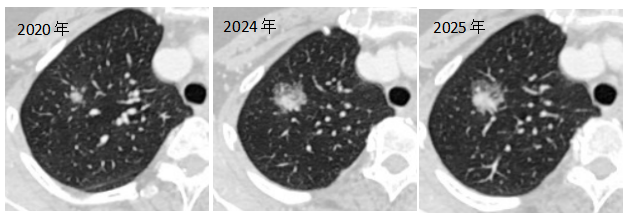

2020年,患者李女士在一次体检中偶然发现自己的右上肺竟然长了一个结节,但由于结节较小也没有明显症状,即使医生再三明确叮嘱需要定期复查观察,但李女士并未放在心上,再加上工作生活等多种原因,连续4年李女士都没有前往医院进行CT检查。

直到今年前段时间,李女士由于持续性的胸痛来到茂名市人民医院“广东省人民医院专家门诊”就诊检查时,才发现右上肺的结节直径竟已由4年前的8mm暴增至23mm,初步考虑为肺恶性肿瘤。

▲患者肺结节逐年增大

“如果患者近几年能按时复查,早点发现结节变化,及时进行手术,手术范围会较小,切除的肺组织更少,丢失的肺功能也会更少。"茂名市人民医院胸外科执行主任张升博士在仔细了解患者李女士相关病史及影像学动态变化后惋惜道,“目前肺结节相比之前明显增大,考虑为肺恶性肿瘤的可能性比较大,现在手术需要要切除整个右上肺叶。不过庆幸的是,目前影像学没有看到明显的转移淋巴结,早期肺癌的可能性较大,现在行根治性手术是‘亡羊补牢未迟也’。”